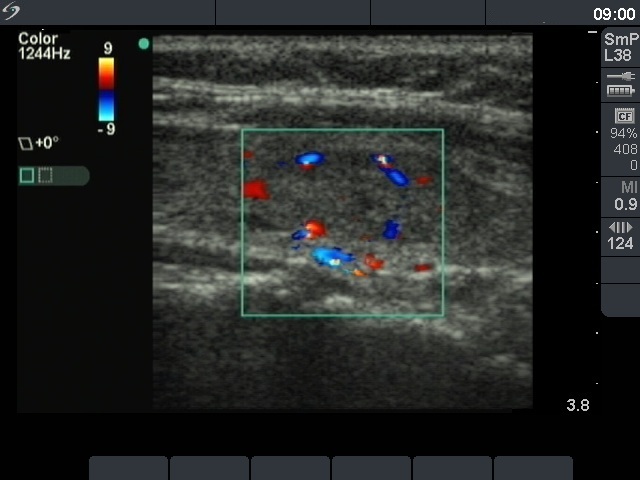

First examination (1st and 2nd rows of images)

Ultrasonography. The thyroid was echonormal. There was a moderately hypoechogenic, inhomogeneous nodule in the part of the left lobe. The nodule presented a type 3 vascular pattern.

Comment. the presence of a halo and a perinodular blood flow significantly increases the possibility of a follicular tumor with the likelihood of around 50%. Nevertheless, great proportion of hyperplastic nodules also exhibit these ultrasound signs. On the other hand, the absence of both a halo and a perinodular blood flow not simply decreases the likelihood of a follicular tumor but makes this possibility very unlikely: less than 2% of such nodules proves to be follicular tumors.